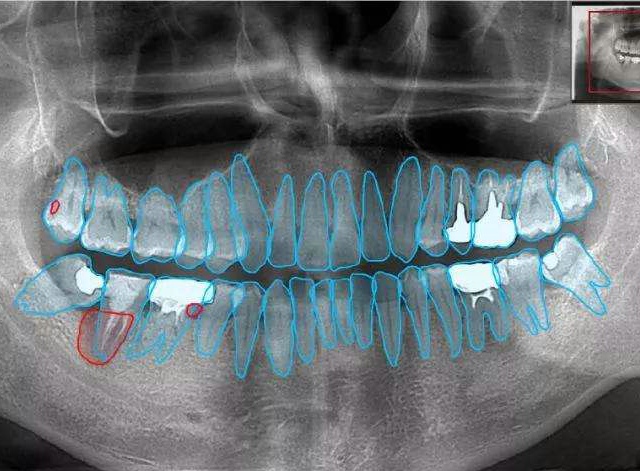

在結(jié)腸鏡插鏡到盲腸時(shí),內(nèi)鏡醫(yī)師留取圖像,此時(shí)智能輔助系統(tǒng)自動啟動,伴隨著腸鏡醫(yī)師的退鏡一起實(shí)時(shí)監(jiān)督腸道內(nèi)有無息肉或病變的出現(xiàn)。當(dāng)人工智能系統(tǒng)懷疑有病變在腸道內(nèi)出現(xiàn)時(shí),會實(shí)時(shí)地發(fā)出警報(bào)聲音提醒腸鏡醫(yī)生注意可能遺漏的病變,并且會實(shí)時(shí)的標(biāo)注出系統(tǒng)高度懷疑有病變的部位,幫助內(nèi)鏡醫(yī)生發(fā)現(xiàn)更多有潛在危險(xiǎn)性的病變,做到結(jié)直腸癌的早預(yù)防、早發(fā)現(xiàn)和早治療。